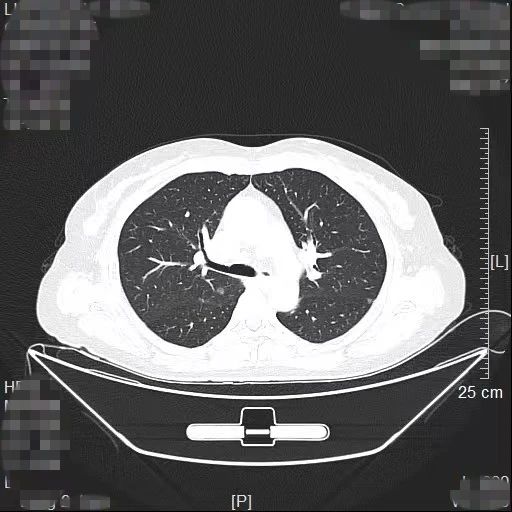

患者林女士今年65岁,长期旅居国外的她在回国后常规体检时查出右肺有2个高危的磨玻璃结节,慕名找到我院胸部肿瘤外科方卫民主任医师。医生团队详细分析了患者的肺部CT及三维重建结果,发现2个结节分别位于右上肺后段边缘及右中肺叶中央,如果直接采用手术切除的方法,要多切除整个右肺中叶,将损失较多的正常肺组织,影响生活质量,得不偿失。

三维重建结果